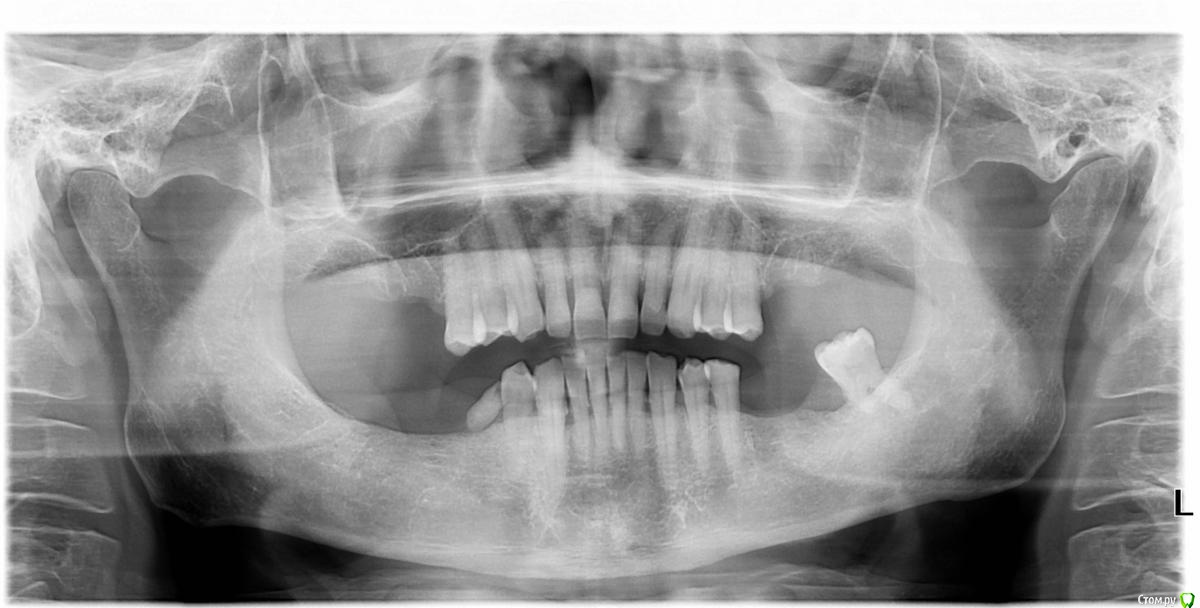

greenspider Опубликовано 9 февраля, 2020 Автор Поделиться Опубликовано 9 февраля, 2020 фото зубов плзпрошу прощения. вот фото: Ссылка на комментарий